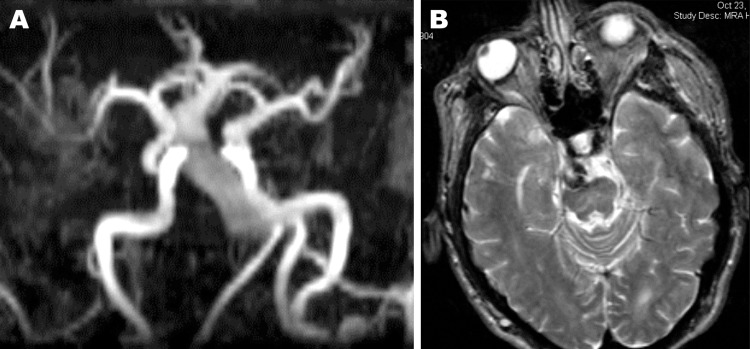

This patient presented with headaches in March of 2005. The medical history was significant for Fabry’s disease and was post two renal transplants. Previous MRIs showed an enlarged basilar artery. At the time, diffusion weighted images demonstrated no evidence for an infarct. Noted were significant but stable ischaemic changes in the basal ganglia, thalami and cerebellum (figure 1).

Figure 1.

Fusiform basilar aneurysm on MRA (A) and T2-weighted axial MRI (B).